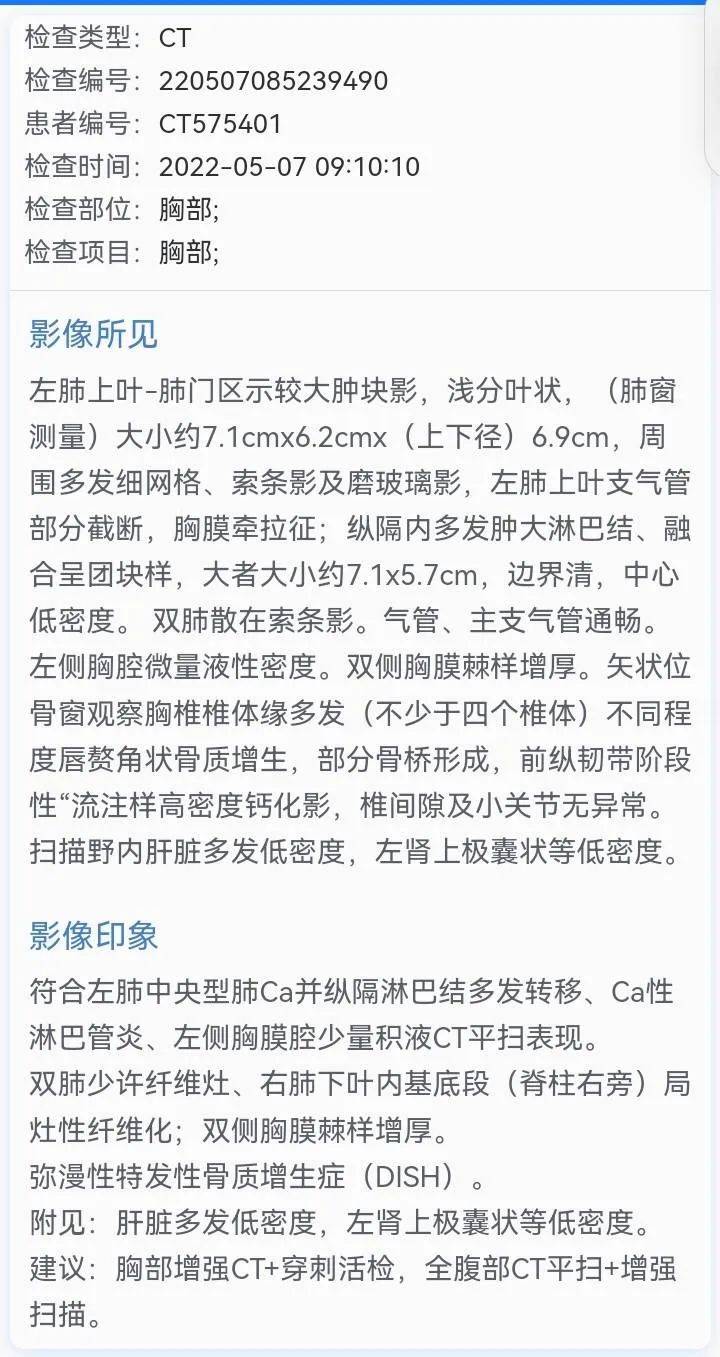

我爸声音嘶哑十余天吃药不见好转,然后到市医院检查,2022年5月7日经CT检查确诊中央型肺癌,肿瘤分期T4N3M1,大小约7.1X6.2X6.9cm,伴淋巴转移,肝脏多发低密度转移。

图片来源:患者提供(点击查看原图)